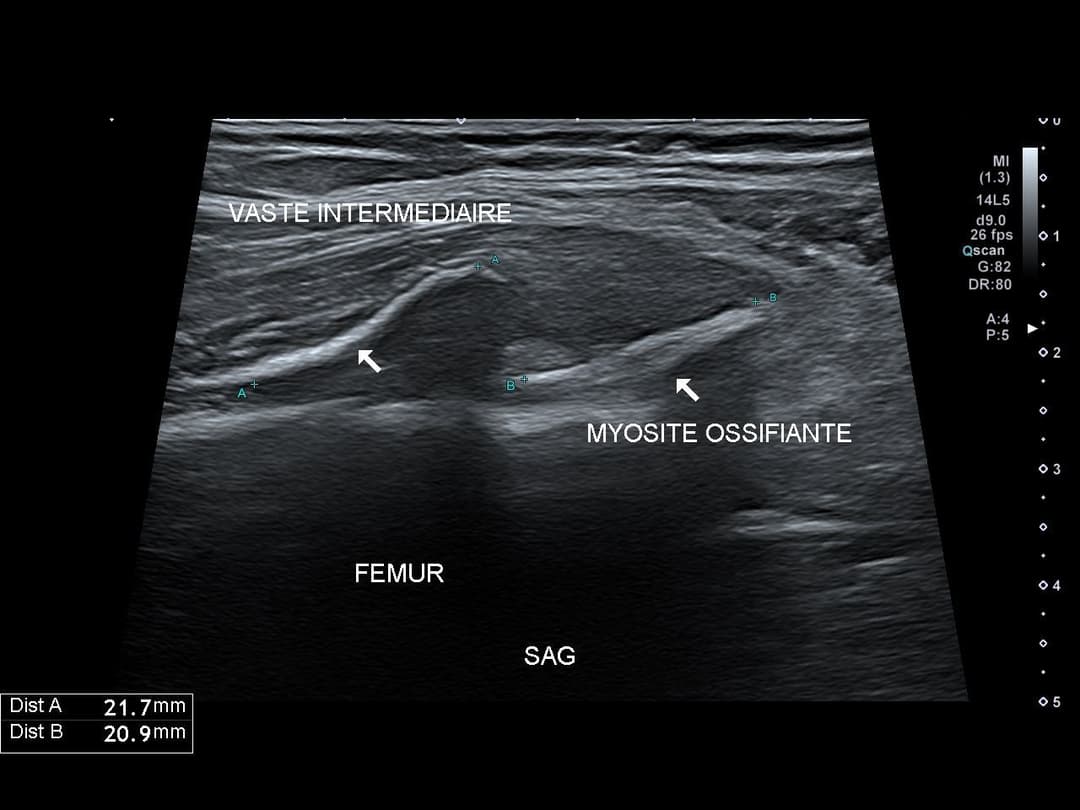

Myosite ossifiante du quadriceps

Patiente de 60 ans présentant une gêne persistante de la cuisse droite malgré un traitement par kinésithérapie bien conduit, suite à une chute à vélo il y a 2 mois

Échographie

Myosite ossifiante du vaste intermédiaire de la cuisse droite à 2 mois